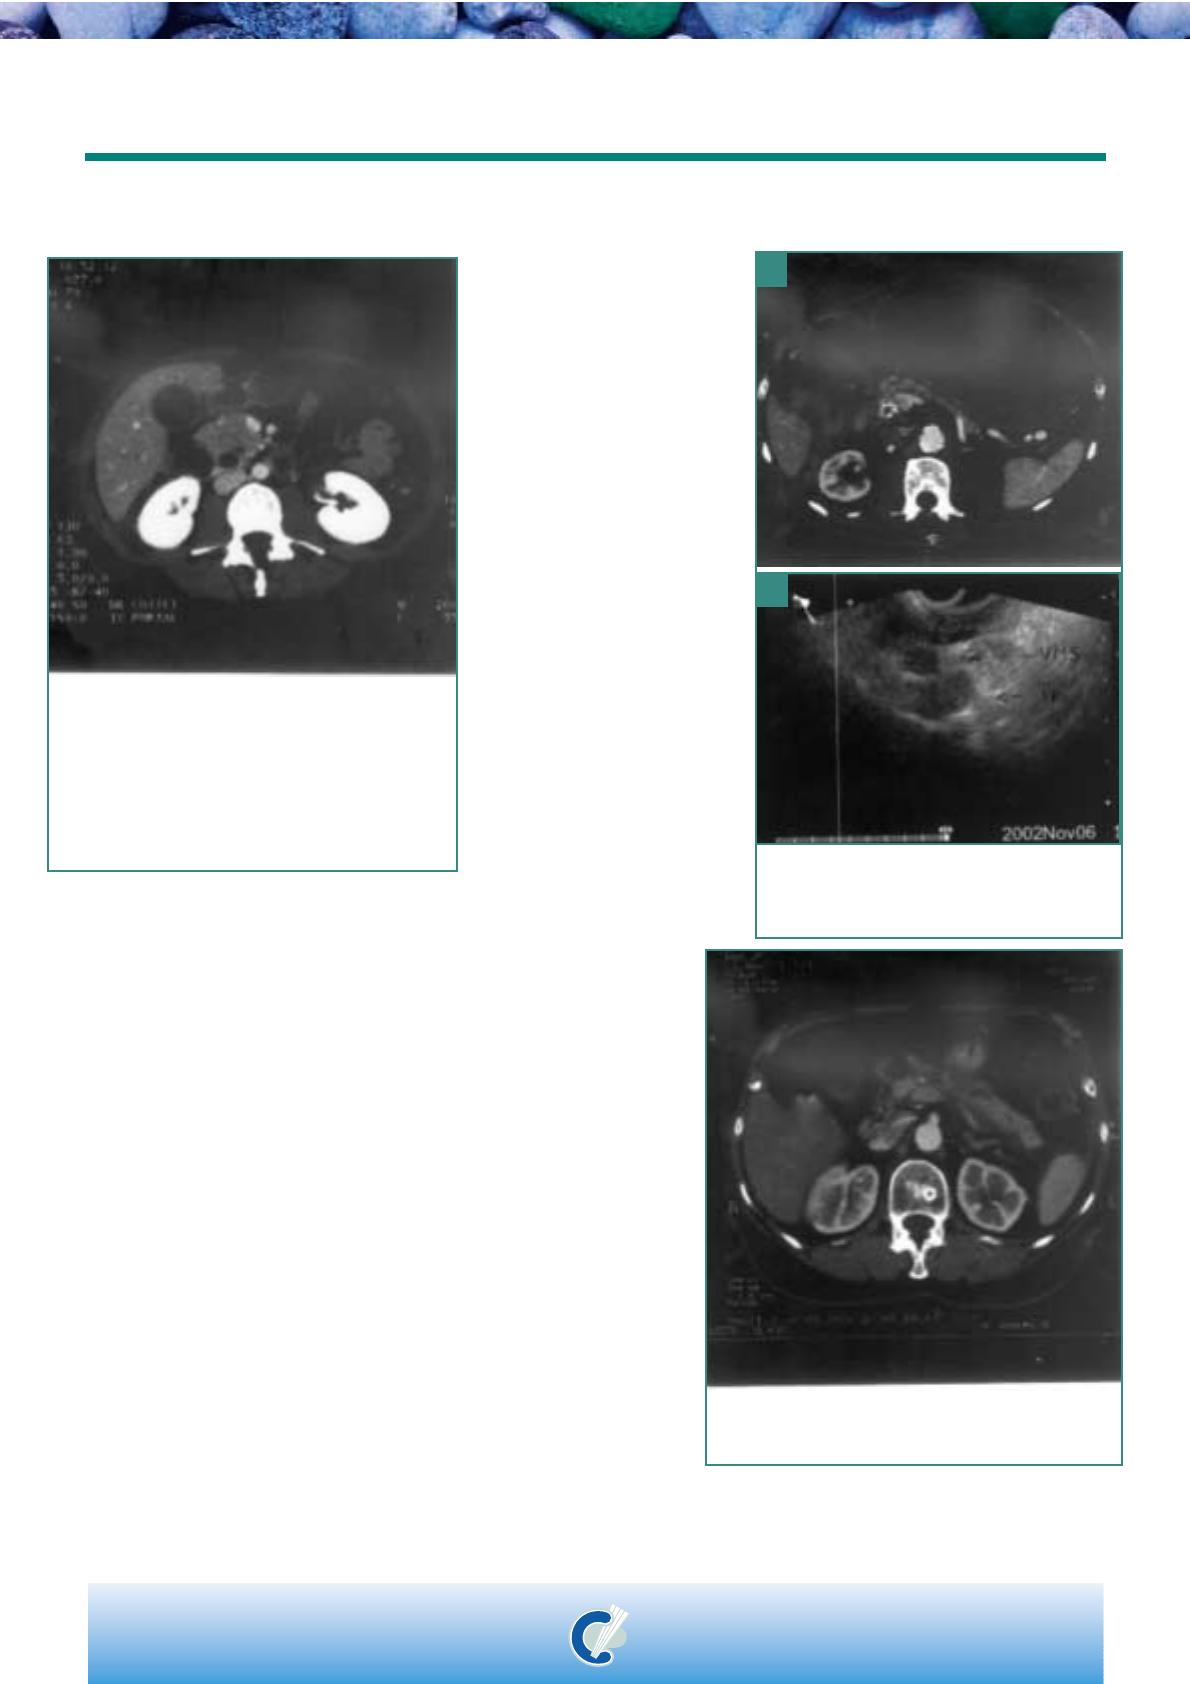

Figure 2 : Cliché TDM réalisé chez une femme de 44 ans

montrant une volumineuse tumeur pancréatique céphalique avec

perte du liseré de sécurité graisseux entre la tumeur et la veine

mésentérique supérieure. L'exérèse a été possible et l'examen

anatomopathologique final a conclu en la présence

dun adénocarcinome du pancréas exocrine envahissant la

musculeuse duodénale.

Figure 3 : Cliché TDM (a) et écho-endoscopie (b) réalisés chez

un patient de 69 ans, faisant suspecter un envahissement

veineux. Lintervention chirurgicale a infirmé cette atteinte et

la duodénopancréatectomie céphalique a pu être réalisée.